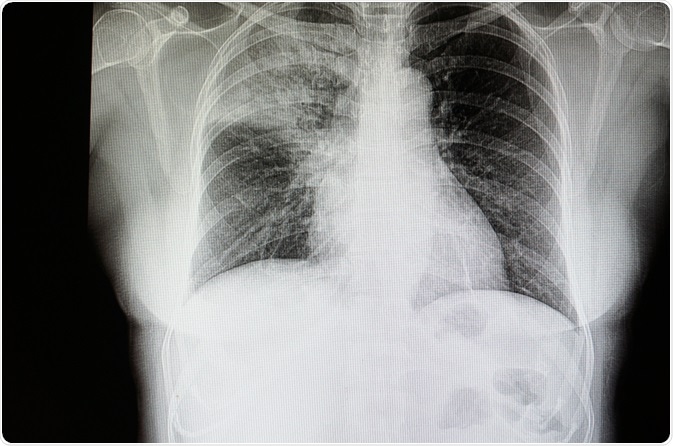

Pneumonia is a common lung infection that affects millions of people worldwide. Pneumonia is most often caused by the bacteria Streptococcus pneumonia, but infection can also be due to a number of viruses, fungi, and mycoplasmas.

Image Credit: Tomatheart / Shutterstock.com